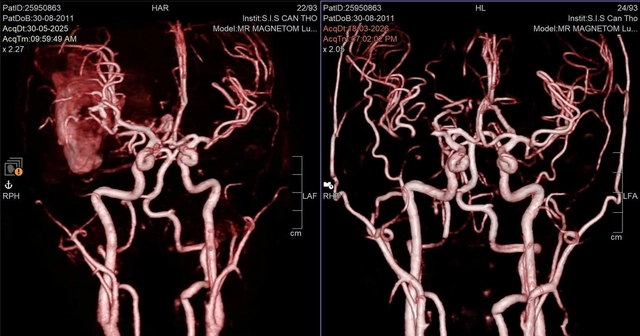

Cứu sống nam sinh hôn mê sâu do vỡ mạch máu não- Ảnh 1.

Hệ thống mạch máu não của bệnh nhân trước và sau khi được can thiệp xử lý túi phình bị vỡ